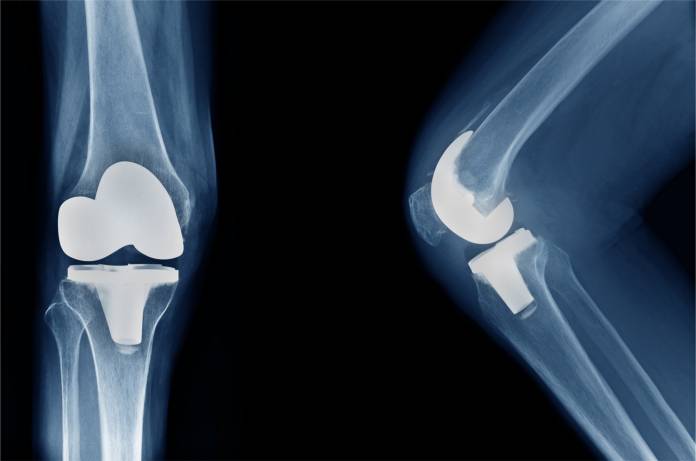

Zum Gelenkersatz gibt es mehrere Prothesenarten von verschiedenen Herstellern. Welche Möglichkeit gewählt wird, hängt von den individuellen Umständen ab, so unter anderem vom Zustand der Gelenkkapsel und der Bänder sowie vom Allgemeinzustand des Patienten. Meist wird eine Total-Endoprothese eingesetzt, bei der die gesamte Verbindung von Oberschenkelknochen und Schienbein erneuert wird (Knie-TEP). Nur manchmal genügt eine Teilprothese.

Die einfachste Art der Total-Endoprothese ist die Oberflächenprothese. Dabei werden die angegriffenen Gelenkflächen aus Knorpel vom Oberschenkelknochen und Schienbein zusammen mit einer dünnen darunterliegenden Knochenschicht abgetragen. Die freiliegenden Knochenflächen werden so bearbeitet, dass sich die Prothese genau einfügt. Diese wird dann an den beiden Knochen befestigt.

Eine markraum-verankerte Prothese wird jeweils tiefer in Schienbein und Oberschenkelknochen befestigt als die oberflächliche Prothese. Die verankerte Prothese kann bei verminderter Knochenstabilität notwendig werden. Ein dornförmiger Aufsatz der Prothese wird bei der Operation in den jeweiligen Knochenmarkraum eingeführt.

Die beschriebenen Prothesen können auf unterschiedliche Art und Weise eingepflanzt werden. Häufig vorgenommen wird eine zementfreie Verankerung, wenn die Prothese passgenau in den Knochen eingefügt wird. Hier dauert die Einheilung mehrere Wochen, da das Knochengewebe um die Prothese, die eine raue Oberfläche besitzt, herum wachsen muss. Möglich ist auch eine Einzementierung der Materialien mit speziellem Kunststoff (so genannter Knochenzement). Dieser verhärtet sich nach der Verarbeitung rasch, so dass das betroffene Bein bald wieder belastet werden kann. Bisweilen kommen beide Varianten an einem Kniegelenk zum Einsatz, wenn an einem Ende eine Einzementierung, am anderen Ende jedoch eine zementfreie Verankerung vorgenommen wird.